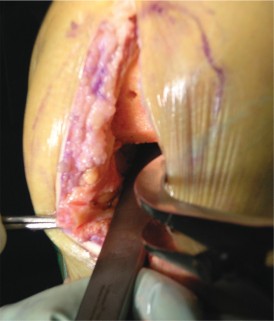

الوصول إلى المفصل (الشقوق):

يستخدم الأستاذ الدكتور محمد هطيف عادةً نهجًا جراحيًا طفيف التوغل (abbreviated trivector approach) للوصول إلى الركبة.

- يتم عمل شق جراحي يبدأ من الجزء الإنسي للحدبة الظنبوبية ويمتد إلى الجزء العلوي من الرضفة.

- يتم فصل ارتباط العضلة المتسعة الإنسية عن وتر العضلة الرباعية، مع الحرص على عدم تجاوز 3 سم فوق القطب العلوي للرضفة.

- يتم رفع غشاء الأنسجة الرخوة الإنسي بعناية وصولاً إلى الزاوية الخلفية الإنسية للركبة.

- يتم إزالة جزء من الوسادة الدهنية للرضفة.

- تُدفع الرضفة بعد ذلك إلى الميزاب الجانبي وتُثنى الركبة لزيادة كشف المفصل.

مفاتيح النجاح الجراحي (Pearls):

- رفع الرباط الجانبي الإنسي (MCL) بعناية يمنع تمزقه عند تحريك الركبة.

- توسيع الشق الجراحي تدريجيًا عند الحاجة يوفر رؤية أفضل في الحالات الصعبة.